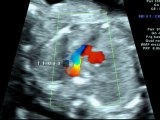

Aloka- Tetralogia di Fallot

Tetralogia di Fallot e stenosi dell'arteria polmonare

Ecocardiografía Fetal: Tetralogia de Fallot

Aloka-Tetrralogia di Fallot con valvola polmonare assente

Tetralogia di Fallot